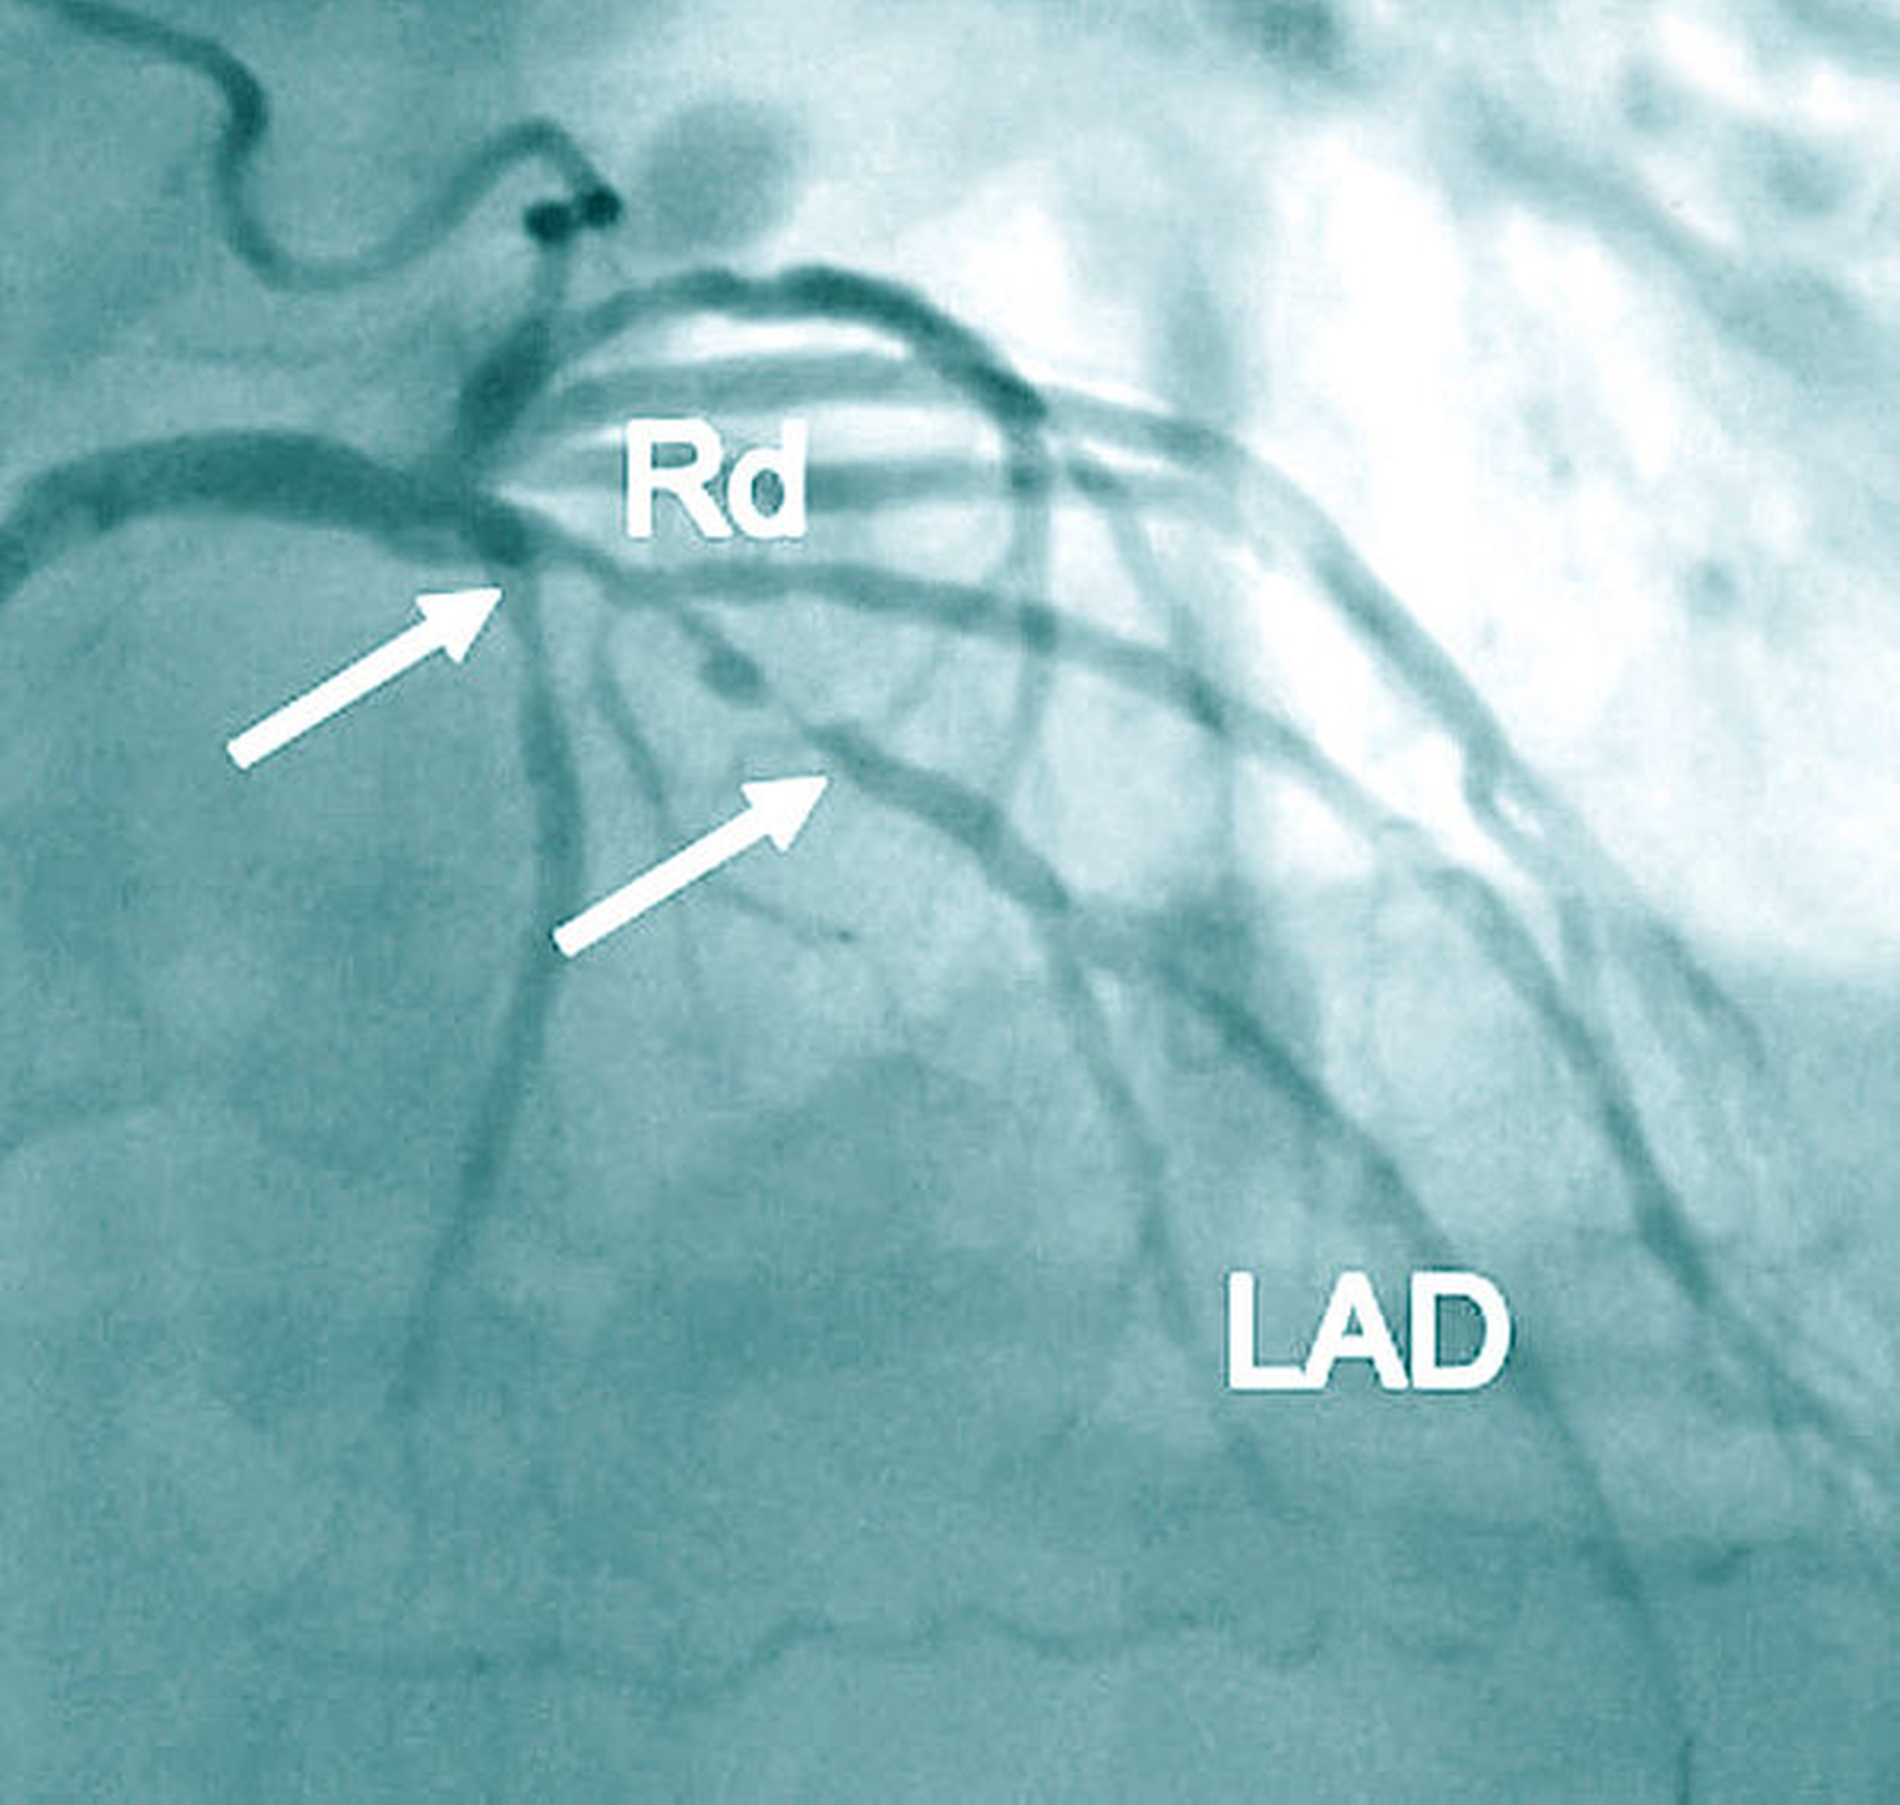

Die KHK ist gekennzeichnet durch arteriosklerotische Veränderungen der Herzkranzgefäße (Abbildung 1a). Die Folge kann eine verminderte Durchblutung und dadurch bedingte Schädigung der Herzmuskulatur sein. Klinische Korrelate für die gestörte Koronardurchblutung sind die Angina pectoris (Brustenge) und Herzrhythmusstörungen bis hin zum plötzlichen Herztod. Ein Herzinfarkt mit nachfolgender Herzinsuffizienz stellt eine bedeutsame Komplikation der KHK dar. Als Therapie kommen bei der Erkrankung der kleineren Gefäße Medikamente (Nitrate, Betarezeptorenblocker, Calcium-Kanal-Blocker) und bei Beteiligung der großen Koronargefäße bevorzugt die Dilatation/Stentversorgung im Rahmen einer interventionellen Therapie oder einer Operation (aortokoronare Bypass-Versorgung) in Betracht (Abbildungen 1b und 1c).